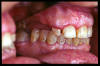

CM Edentulismo parcial, restos radiculares y caries